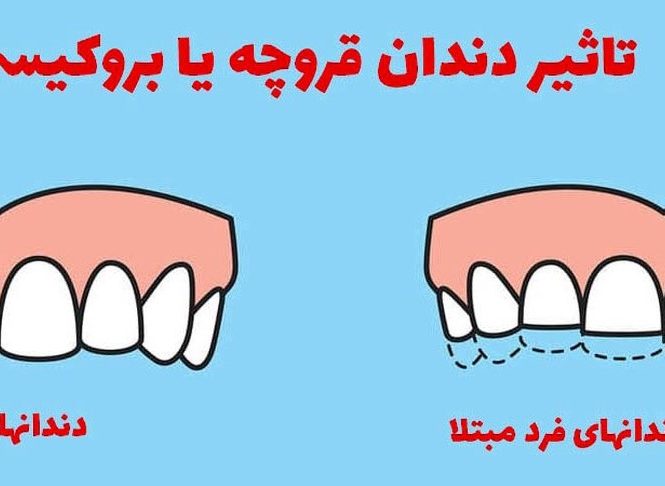

دندان قروچه چیست؟ براکسیسم یا دندان قروچه به معنی عادت فشار دادن یا سایش دندانها به طور ناخواسته…